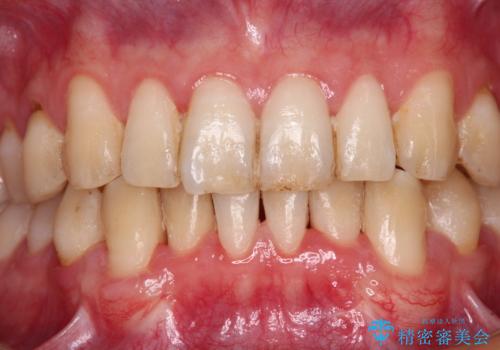

- 下顎犬歯の歯肉退縮を気にして来院された患者様です。

歯磨きの際にしみるとのことで、歯肉移植による根面被覆を行うこととしました。